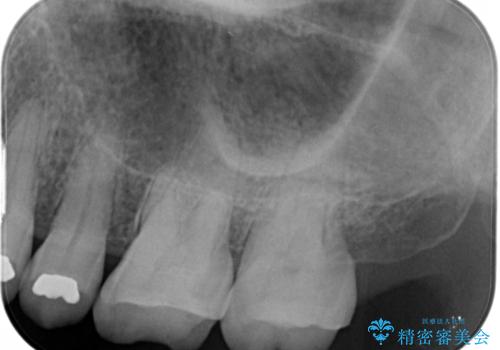

- 以前に異なる種類の材料で継ぎ接ぎ状態で修復されており、隙間のところから虫歯が再発していました。歯の手前側と後方及び内側に亀裂も入っていたため、将来的な虫歯再発のリスク及び歯の破折リスクを最小限にとどめるよう、被せものにて治療を行いました。